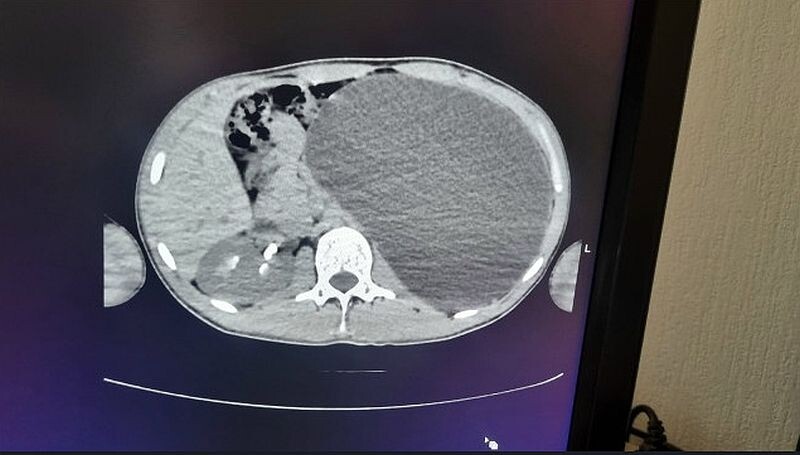

Мы стали обследовать, оказалось, что это гидронефроз левой почки с отсутствием паренхимы (основная ткань органа, выполняющая его функции – примечание)», – отметила врач.

Обследование показало, что почка увеличилась до размеров пятилитровой бутылки. Орган занимал почти всю брюшную полость и сдавливал соседние структуры. В медучреждении подчеркнули, что ситуация была крайне опасной.